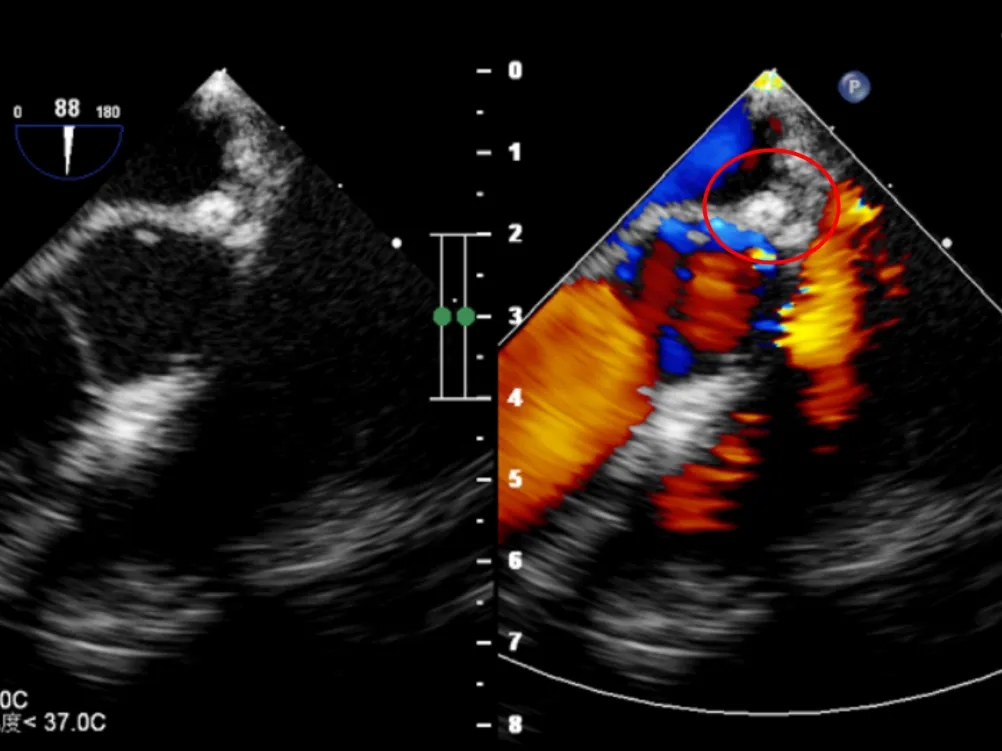

超声下可见左冠状动脉异常增宽

右心房后壁侧可见高速紊乱的血流信号

超声下可见封堵器形态位置正确,未见明显血流通过,封堵器盘面贴合,位置固定